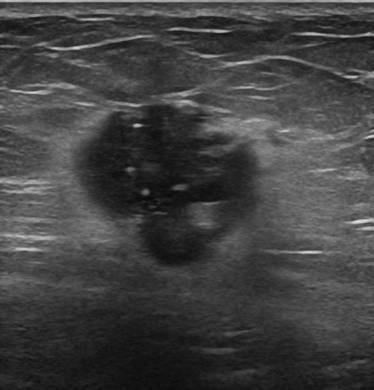

Ung thư vú

» Thông tin: Nữ giới – 51 tuổi.

» Lâm sàng: Khối tuyến vú.